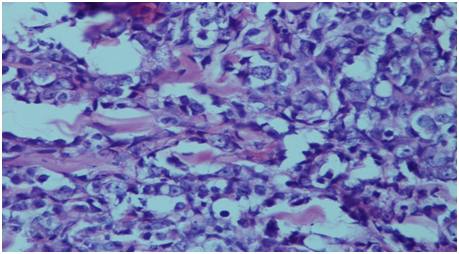

Figure 2 Histopathology of the skin nodule showing infiltration by prostatic adenocarcinoma.

Prostatic carcinoma is common cancer in elderly men. It mostly metastasis to bone, lung, liver, adrenal and lymph nodes. Metastasis to skin is rare and accounts for less than 1% of cutaneous metastases,2 with less than 80 cases published in the literature.4,5 Clinically, patients present as asymptomatic papule, nodule or occasionally sclerodermoid lesion over suprapubic region, lower abdominal area, inner aspect of thigh and genitalia.6 Rare site of cutaneous metastasis include chest, scalp and face.1 The probable route of spread are dissemination vialymphatics and spread through perineural lymphatics.6,7 The cutaneous metastasis may resemble angiosarcoma, cellulitis, mammary Paget’s disease, sebaceous cyst, Sister Joseph nodule, basal cell carcinoma, pyoderma, morphea, and trichoepithelioma.6 The definite diagnosis is done by skin biopsy. The tumour cells show positivity for PSA and cytokeratin. The serum PSA levels are also markedly elevated in these cases. The cutaneous metastasis represents advanced stage of the disease and associated with poor prognosis. Most of the patients die within six months of diagnosis.3 The treatment at this stage is palliative care which includes keeping the lesion dry and clean (Figure 1 & Figure 2).